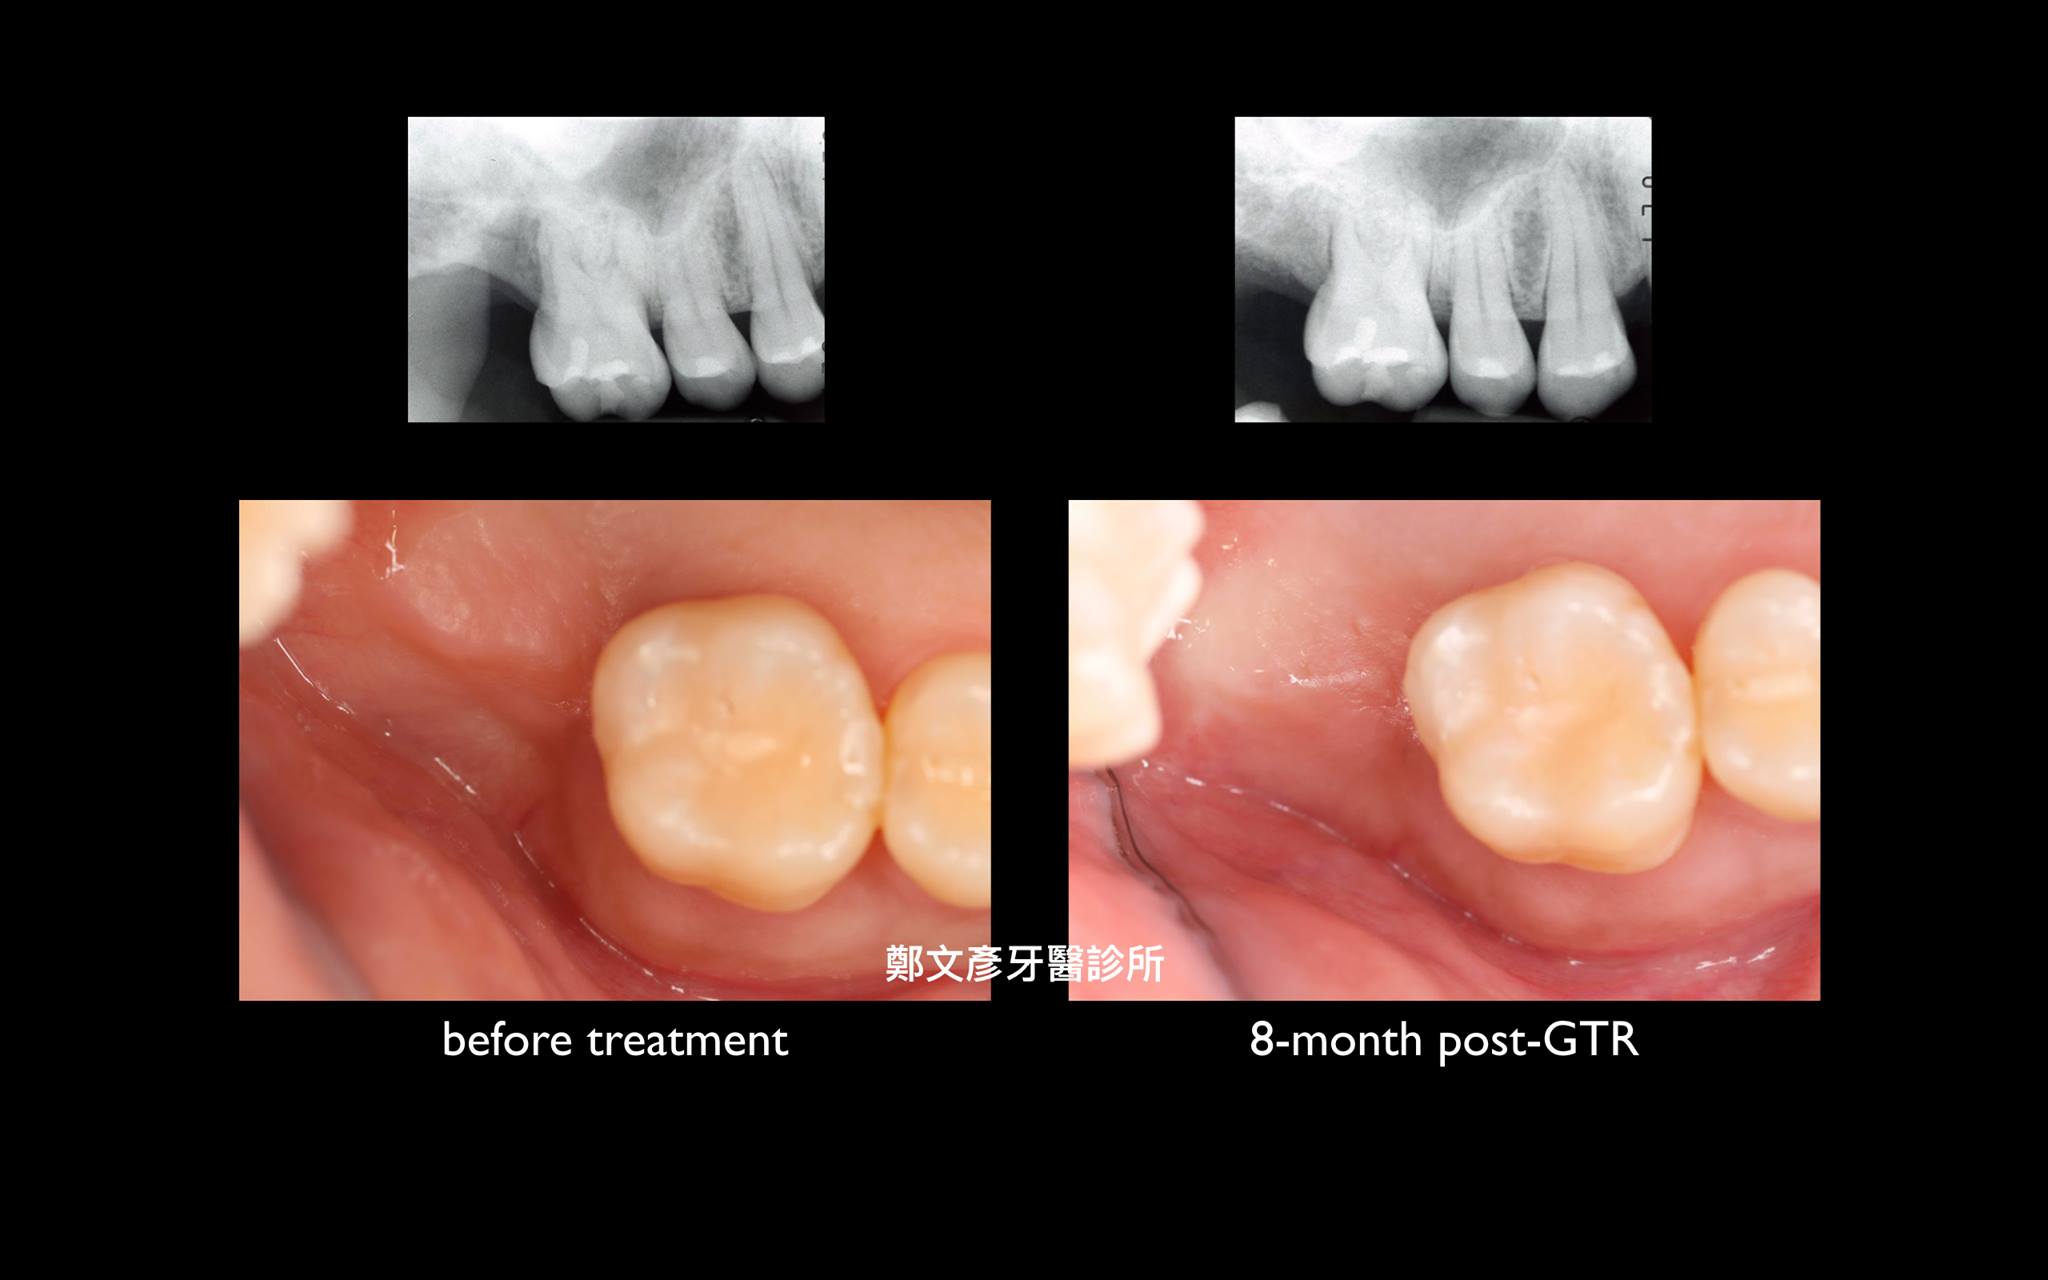

牙周再生補骨手術 ( GTR )

再生補骨